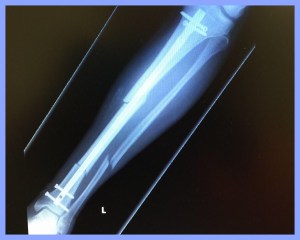

After 8 hours in the ER and 2 hours of surgery, I went home the next afternoon with the titanium rod and screws you see below. The hardware is permanent.